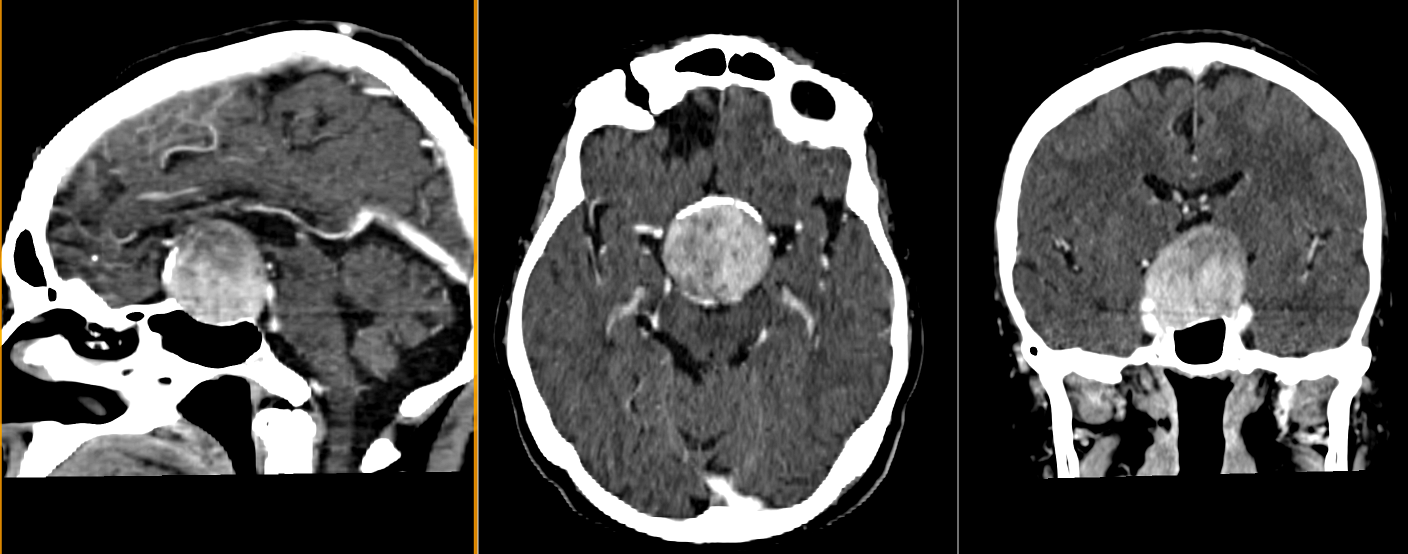

- Adamantinomatose: cele mai frecvente, întâlnite predominant la copii. Prezintă chisturi mari, calcificări extinse și un epiteliu scuamos, cu arii keratinoase (keratină lamelară) și colesterol în interiorul chisturilor.

Localizare și creștere tumorală

Craniofaringioamele au localizare predominant supraselară, dar pot avea extensii variabile în zona selară, hipotalamică, chiasmatică și ventriculară. Frecvent, tumora comprimă structurile din vecinătate, inclusiv hipotalamusul, hipofiza, chiasma optică, arterele cerebrale anterioare și ventriculii laterali. Această poziționare explică simptomatologia complexă, care poate include tulburări endocrine, neurologice și vizuale.

- Imagistica cerebrală (RMN și CT) este esențială. RMN-ul evidențiază tumora în detaliu, oferind informații despre extindere și relațiile cu structurile adiacente. CT-ul evidențiază mai bine calcificările caracteristice craniofaringioamelor adamantinomatose.